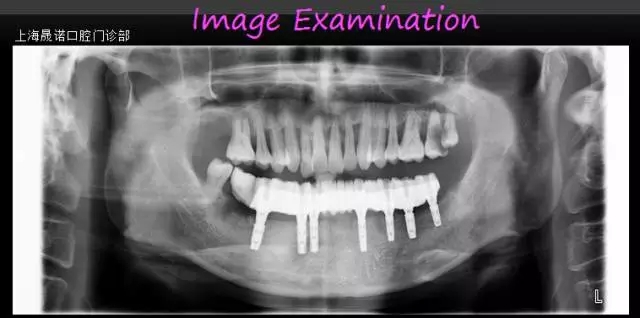

術(shù)前影像檢查分析

640.webp (1).jpg

640.webp (2).jpg

雙側(cè)后牙區(qū)唇側(cè)不規(guī)則骨缺損,最大骨寬度為7mm,高度尚可。CBCT掃描顯示下頜余留牙牙周支持組織重度喪失和伴根尖周病變、繼發(fā)齲。